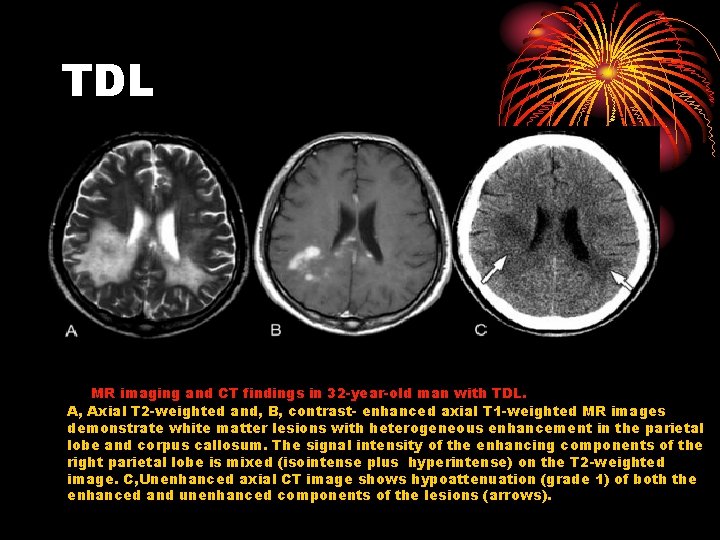

TDL MR imaging and CT findings in 32 -year-old man with TDL. A, Axial T 2 -weighted and, B, contrast- enhanced axial T 1 -weighted MR images demonstrate white matter lesions with heterogeneous enhancement in the parietal lobe and corpus callosum. The signal intensity of the enhancing components of the right parietal lobe is mixed (isointense plus hyperintense) on the T 2 -weighted image. C, Unenhanced axial CT image shows hypoattenuation (grade 1) of both the enhanced and unenhanced components of the lesions (arrows).